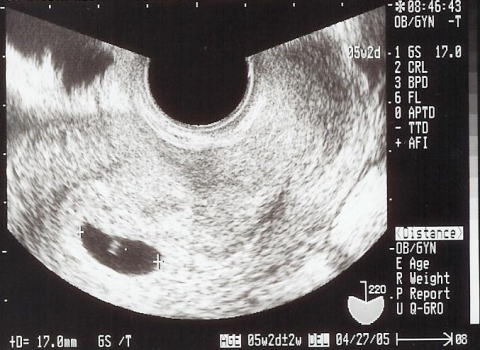

4週2日

パパも一緒にamだけ仕事をお休みして、病院の婦人科へ行き、ママの正常な妊娠が確認されました。写真の中に見える黒い豆がshigeruの入る袋なんだって!shigeruはまだ見えないし、パパもママも実感がわきません。